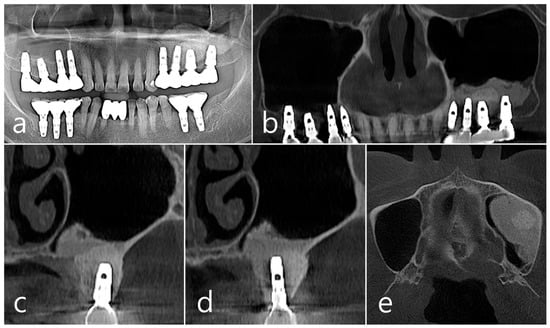

In the panoramic radiography and CBCT images taken after the prosthesis was delivered, no unusual radiographic image was observed at the bone graft site in the left maxillary sinus (Figure 3a,b). In the coronal images of the CBCT scans in #25 and #26 implants, no specific finding was found at the bone graft site of the maxillary sinus, and there was no thickening of the sinus membrane (Figure 3c,d). A well-consolidated sinus graft was observed on the axial image of CBCT (Figure 3e). The patient was checked up twice a year, and panoramic radiography and CBCT were taken 1 year after prosthesis delivery. Radiolucent images were observed around implants #25 and #26 (Figure 4a–d). A circular radiolucent image was observed in the axial image of CBCT (Figure 4e).

Figure 3. (a,b) In the panoramic radiography and CBCT images taken after the prosthesis was delivered, no special radiographic image was observed at the left sinus augmented site; (c,d) In coronal images of CBCT scanned in #26 and #25 implants, a homogenous radiographic density was observed at the sinus augmented site, and there was no thickening of the sinus mucosa; (e) A well-augmented sinus graft was observed in CBCT axial image.

Figure 4. (a,b) In the panoramic radiography and CBCT images taken 1 year after prosthesis delivery, unusual radiolucent images were observed around implants #25 and #26; (c,d) Radiolucent images around #26 and #25 implants were observed. The buccal cortical plate was lost. However, the appearance of the sinus graft was well maintained, and sinus mucosal thickness was normal; (e) A circular radiolucent finding was observed in the axial image of CBCT.